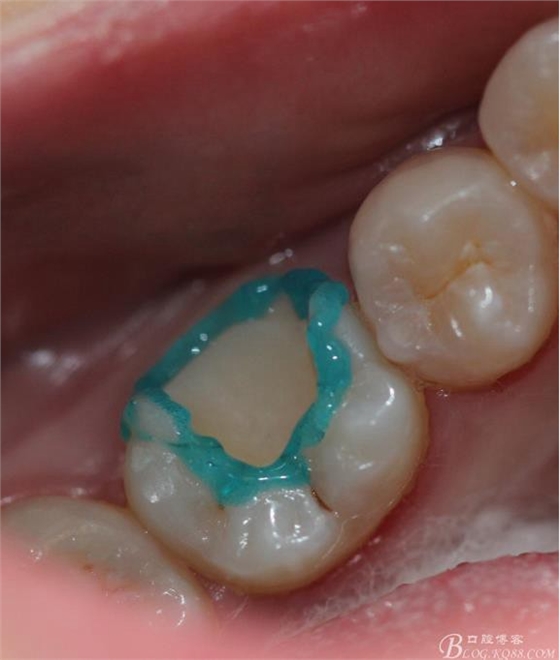

牙體隔濕酸蝕 牙釉質(zhì)15s 牙本質(zhì)20s進(jìn)行濕粘接(不要吹太干)

大家伙都知道,我重復(fù)一下!